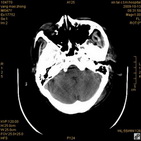

术前CT

术前CT1 术前CT2 术前CT3 术前CT4